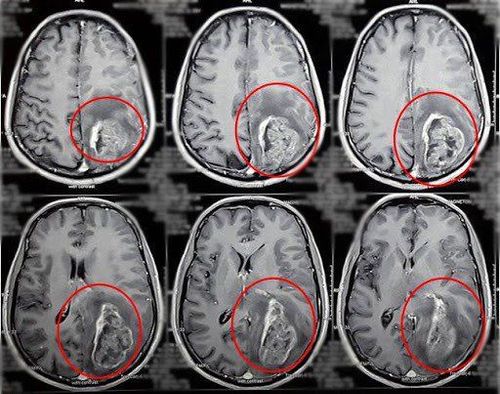

- U trong não:

+ Di căn não: Theo đường máu, theo đường dưới nhện.